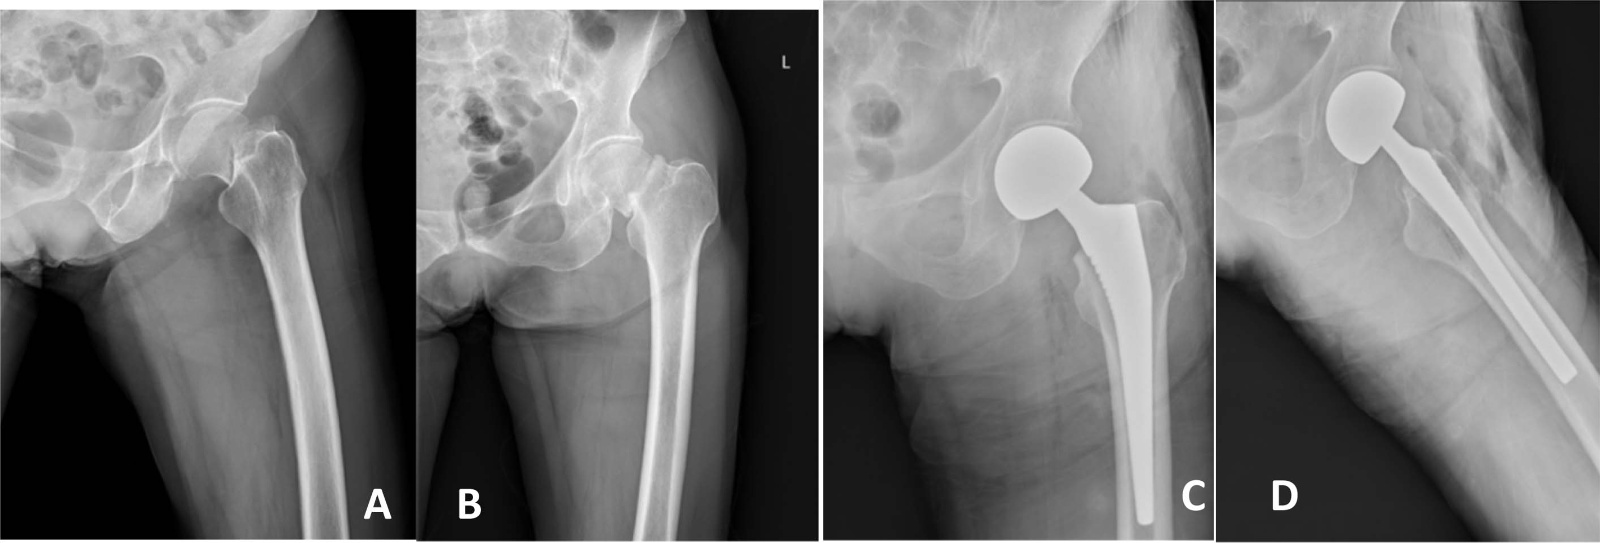

典型病例影像学表现见图1~5图1为76岁女性右侧股骨颈骨折(Garden Ⅲ型)患者,DAA入路半髋关节置换术前X线示骨折断端部分错位,术后X线示假体位置良好,股骨近端微裂予钢丝捆扎固定;图2为83岁女性左侧股骨颈骨折(Garden Ⅳ型)患者,术后X线示假体位置良好;图3为75岁男性右侧股骨颈骨折(Garden Ⅱ型)患者,术后假体位置满意;图4为73岁女性左侧股骨颈骨折(Garden Ⅲ型)患者,术后假体匹配良好;图5为80岁男性右侧股骨颈骨折(Garden Ⅱ型)患者,术后假体位置正常。

Figure 4. X-ray films before and after surgery of a 73-year-old female patient with left femoral neck fracture (Garden type III) A, B: Before surgery; C, D: After surgery

4. 73岁女性左侧股骨颈骨折(Garden Ⅲ型)患者手术前后X线片A、B:术前;C、D:术后